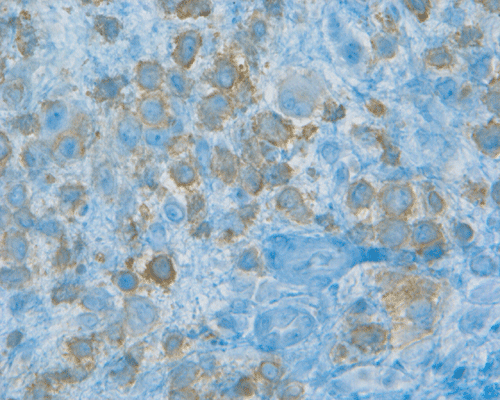

K. S100 |

L. CD1a |

Morphologic features are often sufficient to make an accurate diagnosis. Typical lesions are composed of medium sized to large Langerhans’ cells mixed with non-neopalstic inflammatory cells. The amount of eosinophils can vary from none 3 or scant to substantial. The Langerhans’ cells have only slight degree of atypia. Many of the nuclei have a characteristic deep groove parallel to the long axis, the so-called “coffee bean” nuclei. The amount of cytoplasm is usually moderate. Histiocytes (macrophages) are usually present and can be multinucleated. When histiocytes are present in large amount, they may make the diagnosis difficult. Similar to their non-neoplastic counterparts, tumor cells in Langerhans’ cell histiocytosis are positive for CD1a and S100 by immunohistochemistry. Histiocytes, on the other hands, are negative for S100 and CD1a 4, 5, 6 CD68 is helpful but not entirely specific in separating histiocytes from tumor cells in Langerhans’ cell histiocytosis. The proliferating fraction of can be recognized by immunohistochemistry for Ki67 (MIB-1) 6.